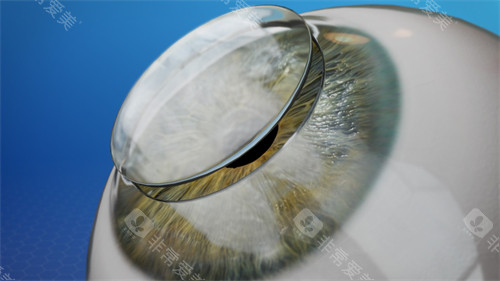

技术亮点:保留健康内皮层,排斥率≤5%,1个月即可拆线

含金量:飞秒激光辅助切口(精度0.1mm),术后散光降低40%

黑科技:3mm微切口植入,无需缝合,术后次日可视物,适合大泡性角膜病变

飞秒激光移植系统实现微米级切割,供体利用率提升40%